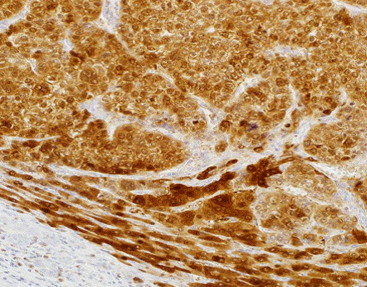

Hepatocellular carcinoma tissue stained with Arginase 1

Arginase-1 is an enzyme that plays a key role in the liver's urea cycle, helping to convert l-arginine into l-ornithine and urea.Arginase-1 is expressed in liver cells of normal liver tissue, and the positive expression rate is 100% in highly differentiated HCC cells, and 85% in poorly differentiated HCC cells.Rare expression in other tumors.